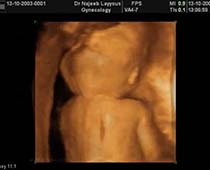

- Fetal Parts Ultrasound Scan Photos

- 3D Fetal Limbs Ultrasound Scan Photos